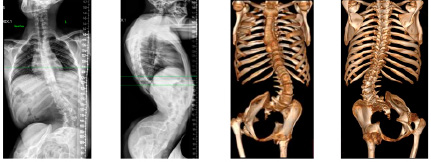

Любого доктора можно быстро подготовить как рентгенлаборанта и дать необходимые знания для оценки рентгенограмм.

Изучение проблемы низкого качества рентгенограмм на Вашем оборудовании.